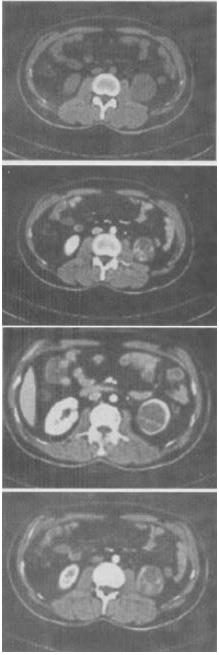

女,63岁,左腰部隐痛不适1个月余,CT平扫+增强如图所示,最可能的诊断是()。

A:左肾下极囊肿

B:左肾下极错构瘤

C:左肾下极癌

D:左肾下极脓肿

E:左肾下极淋巴瘤